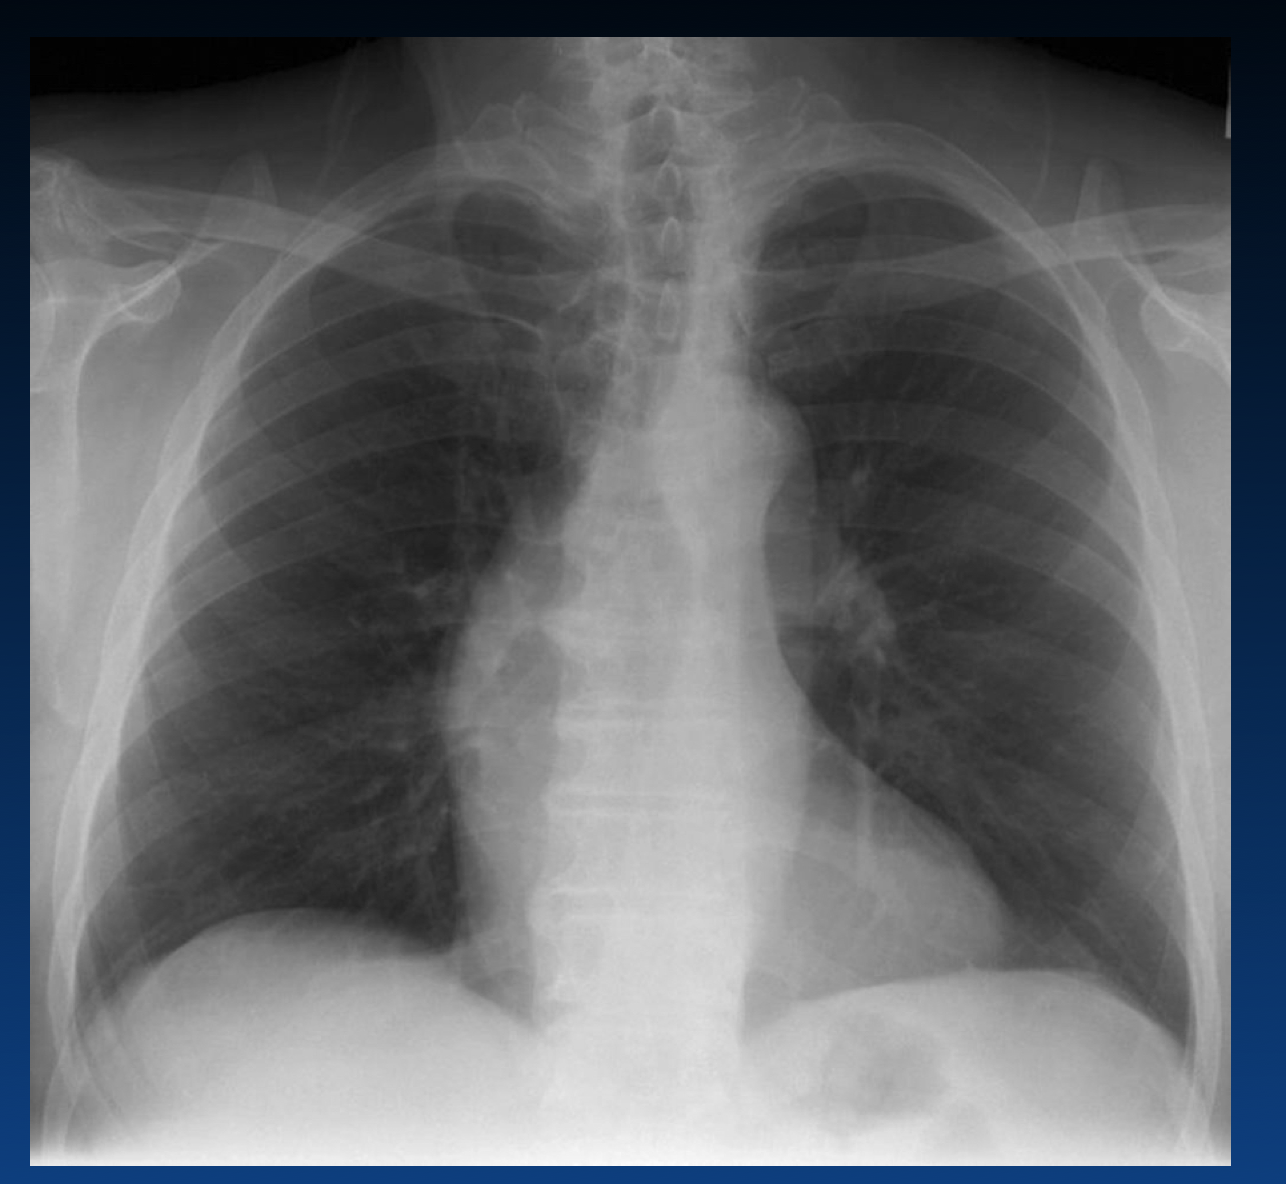

What are the reasons for increased CTR?

What is the Cardiothoracic Ratio?